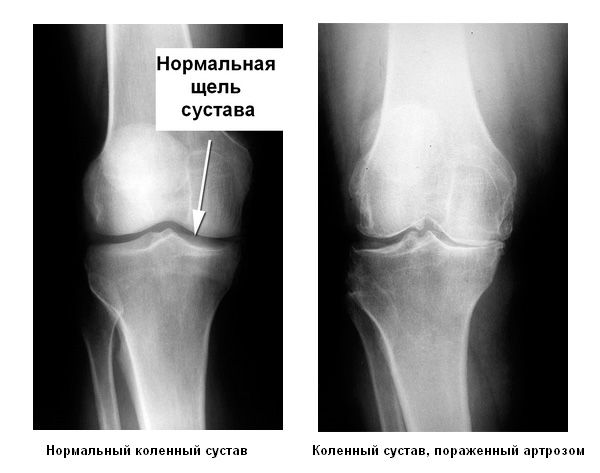

Артроз суставов является заболеванием, которое означает разрушение хрящевой ткани в суставах. Он может возникнуть в руках, в ногах, а также в позвоночнике. Это достаточно серьезный диагноз, который проявляется сильной болью, а в дальнейшем ограничением подвижности. Стоит обратить внимание на тот момент, что разрушение тканей необратимо, поэтому необходимо обращаться к специалисту как можно быстрее.

Для того чтобы лечить артроз народными средствами, необходимо понимать, с чем придется справляться. Основная симптоматика — это боль. Она может возникать сначала только при движении, а затем быть постоянной. Вместе с ней может быть ограничение подвижности, постепенно хрящ уменьшается и становится невыносимо совершать даже простые движения. Дополнительно идет воспалительный процесс. Он может отражаться на всем организме в виде слабости, лихорадки, усталости.